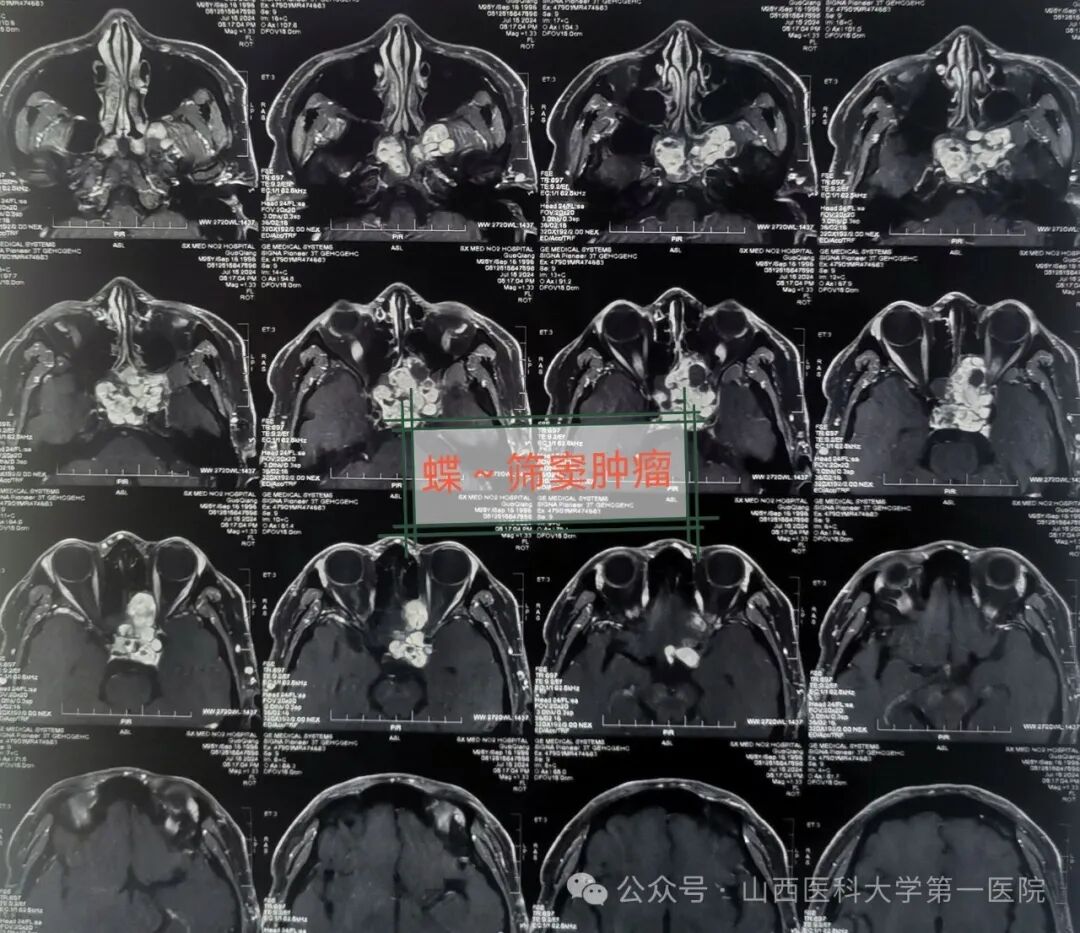

青年男性郭某来自山西晋西北,近2个月来出现头痛头闷、左侧眼睛视物模糊并呈进行性视力下降,且症状越来越加重,于是来到山西医科大学第一医院耳鼻咽喉-头颈外科就诊,经过医生检查后初步诊断为蝶-筛窦肿瘤,且肿瘤侵犯眼眶、中颅底。

医生通过检查发现郭某一侧眼球明显向前外方突出,眼球活动有受限,视力处于急剧下降状态,鼻窦冠状位CT与MRI提示:蝶-筛窦内充满混杂密度肿物阴影,眼眶中颅底受压,考虑鼻窦占位性病变而引起。近日在全麻下行鼻内镜鼻窦肿瘤涉眶与颅底根治切除手术,由耳鼻咽喉-头颈外科皇甫辉教授主刀,术中显露术野、暴露病变组织,发现病变位居单侧鼻腔筛窦与蝶窦,已侵犯单侧眼眶及球后以及中颅底,病变范围广,内镜下切除鼻腔筛窦与蝶窦病变组织,开放蝶窦,肿瘤侵犯眼眶后、海绵窦被侵犯,暴露颈动脉管、颈内动脉视神经隐窝以及视神经管得以保护,同时做视神经减压,最终完整切除肿瘤,手术获圆满成功。